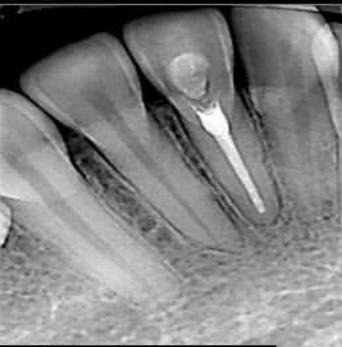

La Endodoncia o Tratamiento de Canal es el mejor procedimiento que puede realizarse en una clínica dental, ya que tiene como finalidad preservar las piezas dentales dañadas, causadas por lesiones inflamatorias en el interior del diente o pulpa dental, evitando así su pérdida. Para ello, se extrae la pulpa dental  (se encuentra en el interior del diente y contiene vasos sanguíneos, nervios y tejido conectivo). y la cavidad resultante, se rellena y sella con material totalmente biocompatible con los tejidos del diente.